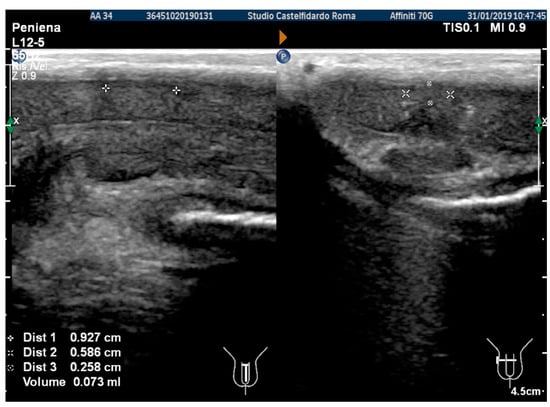

The penile ultrasound showed the following plaque dimensions: 9.27 × 5.86 × 2.58 mm (73 mm3 = volume) (Figure 7).

Figure 7. Ultrasonography of the penis after the 2nd therapy cycle (longitudinal and axial views).